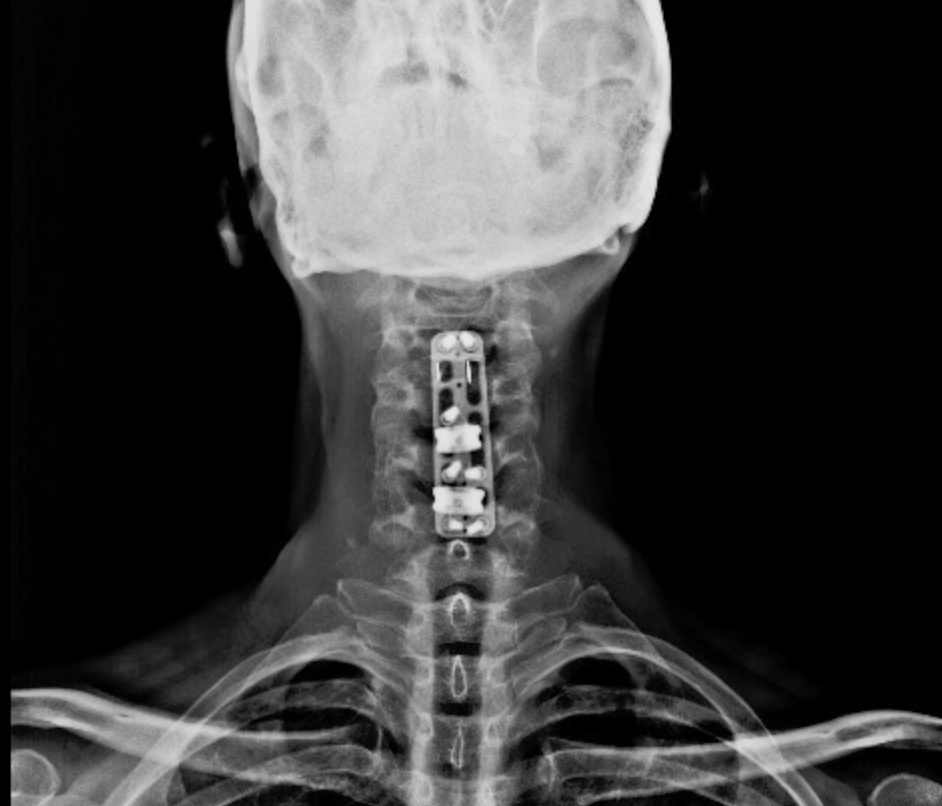

CIRUGIAS

RESULTADOS